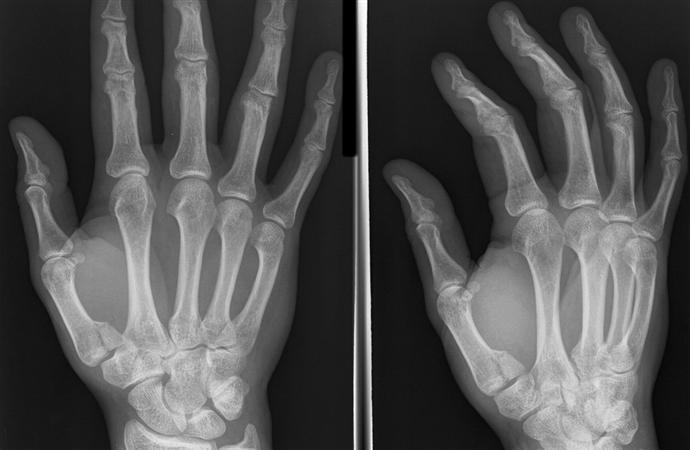

Describe this fracture?

BENNETT

- Oblique fracture through base of the first metacarpal, with dislocation of the radial portion @ articular surface

- produced by direct force applied to end of metacarpal; dorsal capsular structures disrupted by dislocation; marked tenderness along medial base of thumb

• thumb spica x 4 weeks